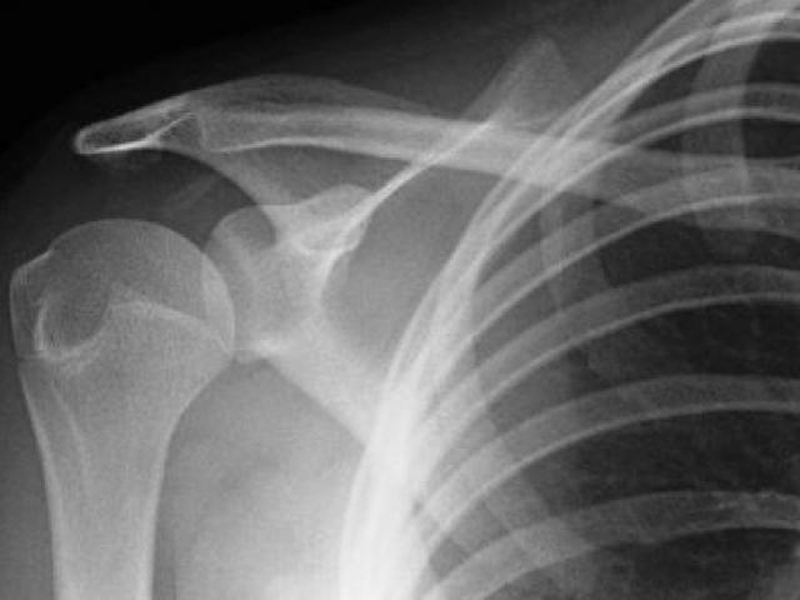

Bán trật khớp vai khó xác định hơn là trật khớp hoàn toàn. Một số trường khớp, phần khớp vai bị trật có thể được nhìn thấy dưới da. Người bệnh có thể cảm thấy đầu khớp di chuyển ra vào trong ổ vai, hạn chế vận động và có thể gây đau.

Điều trị trật khớp vai là tái định vị lại chỏm xương cánh tay vào ổ chảo xương bả vai và đảm bảo nó vẫn ở đúng vị trí. Bác sĩ có thể chẩn đoán bán trật khớp vai bằng siêu âm hoặc chụp X-quang. Việc chẩn đoán chính xác tình trạng của bệnh giúp việc điều trị nhanh chóng hơn. Một số cách điều trị: